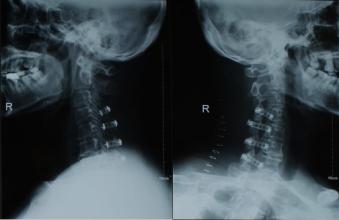

一人一技之李會(huì)全:頸椎病前路減壓植骨融合內(nèi)固定術(shù)

頸椎前減壓必須定位準(zhǔn)確,雖然頸6橫突結(jié)節(jié)最大,可觸摸作為定位標(biāo)準(zhǔn),但通常均以術(shù)中透視或照片確定位置,有C形臂X線透視機(jī)者較為方便。透視或照片前,于頸椎間盤(pán)中插一針頭作為標(biāo)記。椎前筋膜下注射麻藥后,縱行切開(kāi),向兩側(cè)分離不超過(guò)頸長(zhǎng)肌緣,清楚顯出突起而白色椎間盤(pán),骨折椎體亦可顯出變形及出血。如骨折椎體定位明確,可不予透視或照片定位,對(duì)椎間盤(pán)突出或陳舊性骨折脫位,則必需定位。定位確定后,進(jìn)行減壓。

為防止植骨壓縮,可用頸椎前路鋼板固定,現(xiàn)多為鈦質(zhì),術(shù)后仍可行MRI檢查。